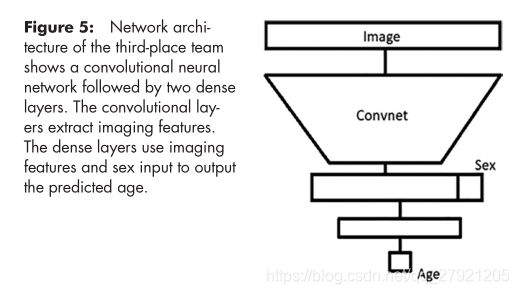

第三名: Felipe Campos Kitamura-MAD=4.382

输入:把训练集划分成5份,每份进行训练,训练集最好的四个网络用于测试,测试结果取平均值。

网络:

整体网络:

提出了新的模块Ice module: